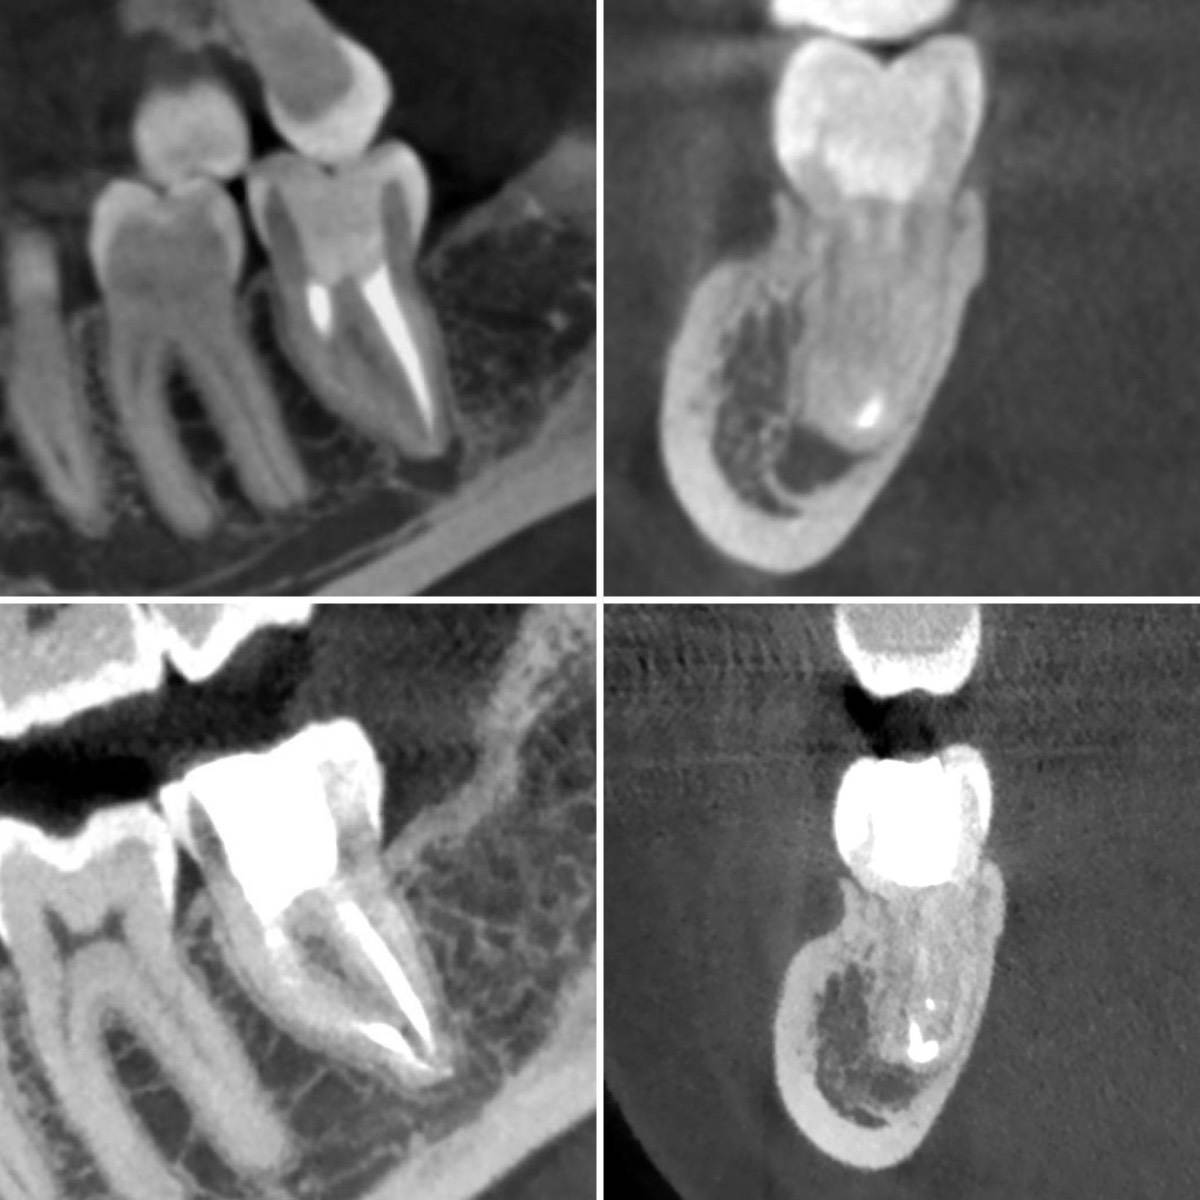

Гарриевич Опубликовано 31 января Автор Поделиться Опубликовано 31 января Когда в твоем кресле оказывается пациент с редким заболеванием «стоматолог-терапевт» работать всегда… легче. Именно! Потому что ты на 100% уверен, что этот человек понимает разницу между «гарантия» и «прогноз», а он на 100% уверен, что ты тот кто ему нужен. Зуб 4.7 со сложной анатомией, ступенькой в мезиальной системе, двойным изгибом, пропущенным каналом и апикальным периодонтитом. Реколл 1 год И сам осмотр через 1 год 4 1 1 Ссылка на комментарий

Гарриевич Опубликовано 18 марта Автор Поделиться Опубликовано 18 марта В 13.03.2026 в 15:26, Doc сказал: Круто! То, что вынимается, доктору вернуть надо или в металлолом сдать? :))) Обычно мы сдаем в чернмет, какие никакие деньги)) Реколл 3 года 1 Ссылка на комментарий